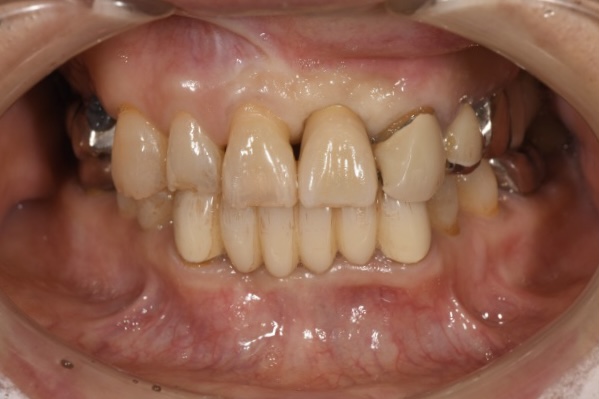

前歯のインプラント治療をする際、審美的に一番大切なのは両隣の歯との歯茎のラインをそろえることとなります。

両隣より歯が長くなってしまうと、大きく歯を見せて笑った時などに不自然にみえてしまいます。

インプラント埋入する場合は大体が状態の悪い歯を抜歯してからのインプラントとなります。

状態の悪い歯はほぼ骨吸収が起こっていますが、インプラントの被せ物と両隣の歯との歯茎のラインを合わせるためには骨の高さが重要となるため、だいたいの症例でGBR(骨造成)が必要となります。

この症例もインプラント埋入時に骨造成を行っています。

見た目だけでなくインプラント治療を行う際は、しっかりと骨がある事、なければ骨を作ることが大切です。